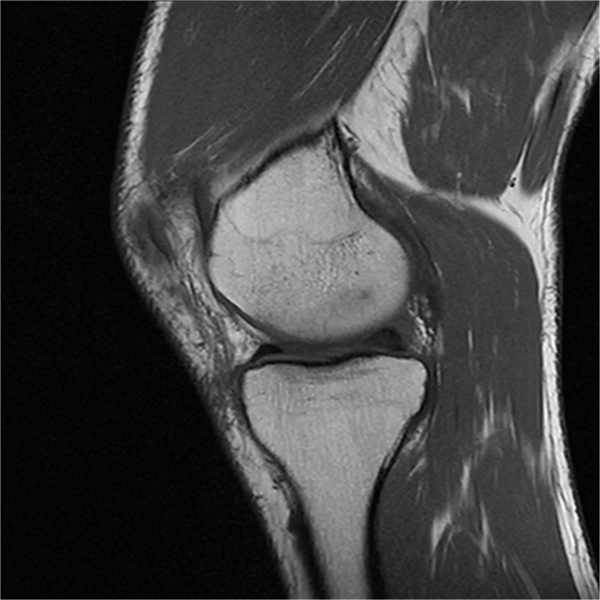

(四)四肢关节及软组织的应用:包括良恶性骨肿瘤、慢性炎症、滑囊积液、关节创伤、关节退变、无菌性坏死等诊断具有其他影像学检查无法比拟的价值。以及全面丰富的动态分析后处理,显著提高小病灶检出率。

部分平扫图像展示